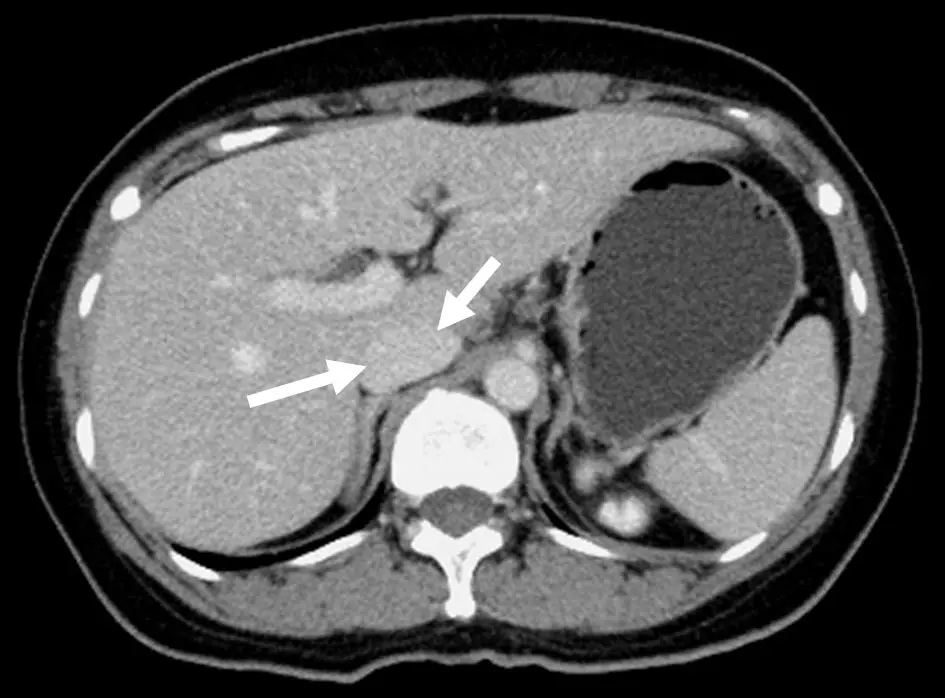

下圖中箭號所指的構造為何?

本圖為腹部軸位 CT,顯示上腹部橫截面,可見以下結構:

- 影像右側(病人右側):大片均勻密度的肝實質(liver parenchyma),可見肝內血管走行。

- 影像左側(病人左側):脾臟(spleen),呈現較肝臟稍低的均勻密度。

- 兩支白色箭號:

- 左側較短箭號(朝右下方指):指向位於肝臟內側、門靜脈(portal vein)走行方向的圓形管狀結構,位於肝門部(porta hepatis)附近。

- 右側較長箭號(朝右上方指):明確指向位於脊椎(vertebral column)右前方的橢圓形低密度管狀結構,此位置即為**下腔靜脈(IVC)**的典型解剖位置。

- IVC 在腹部 CT 上位於脊椎的右前外側,走行於腹膜後腔(retroperitoneal space),因為本圖為非增強或靜脈期掃描,IVC 呈現低密度(血液)的橢圓形截面,明顯與右側的腹主動脈(位於脊椎左前方)相對應。